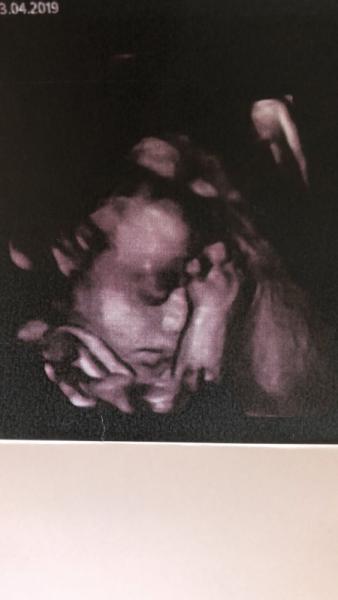

Wie süß!!!! Mich hat die zweite Wrkältung in drei Wochen erwischt Ich hatte heute auch mein 3. Screening. Die kleine Maus hat auch etwa 1400 g Dann gibt es wohl doch noch mehr kleine Mäuse ^^ Hab das Bild auch mal beigefügt sie kuschelt so schön mit ihrem Arm :) Ich wünsche dir noch eine gute Besserung ^^

Bild zu